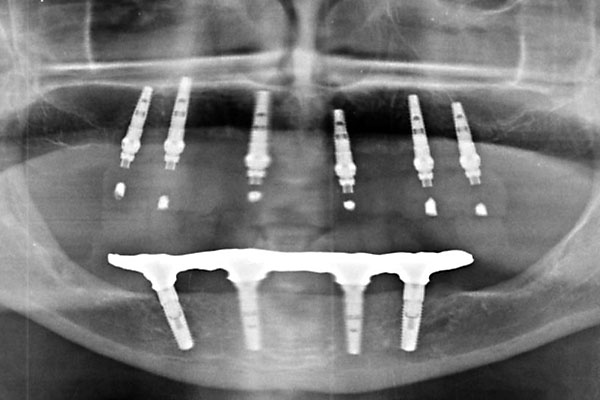

Fall: festsitzender Zahnersatz im Oberkiefer auf 8 Implantaten

FOTO Ausgangsröntgenbild |

FOTO Abschlußröntgenbild der Versorgung |